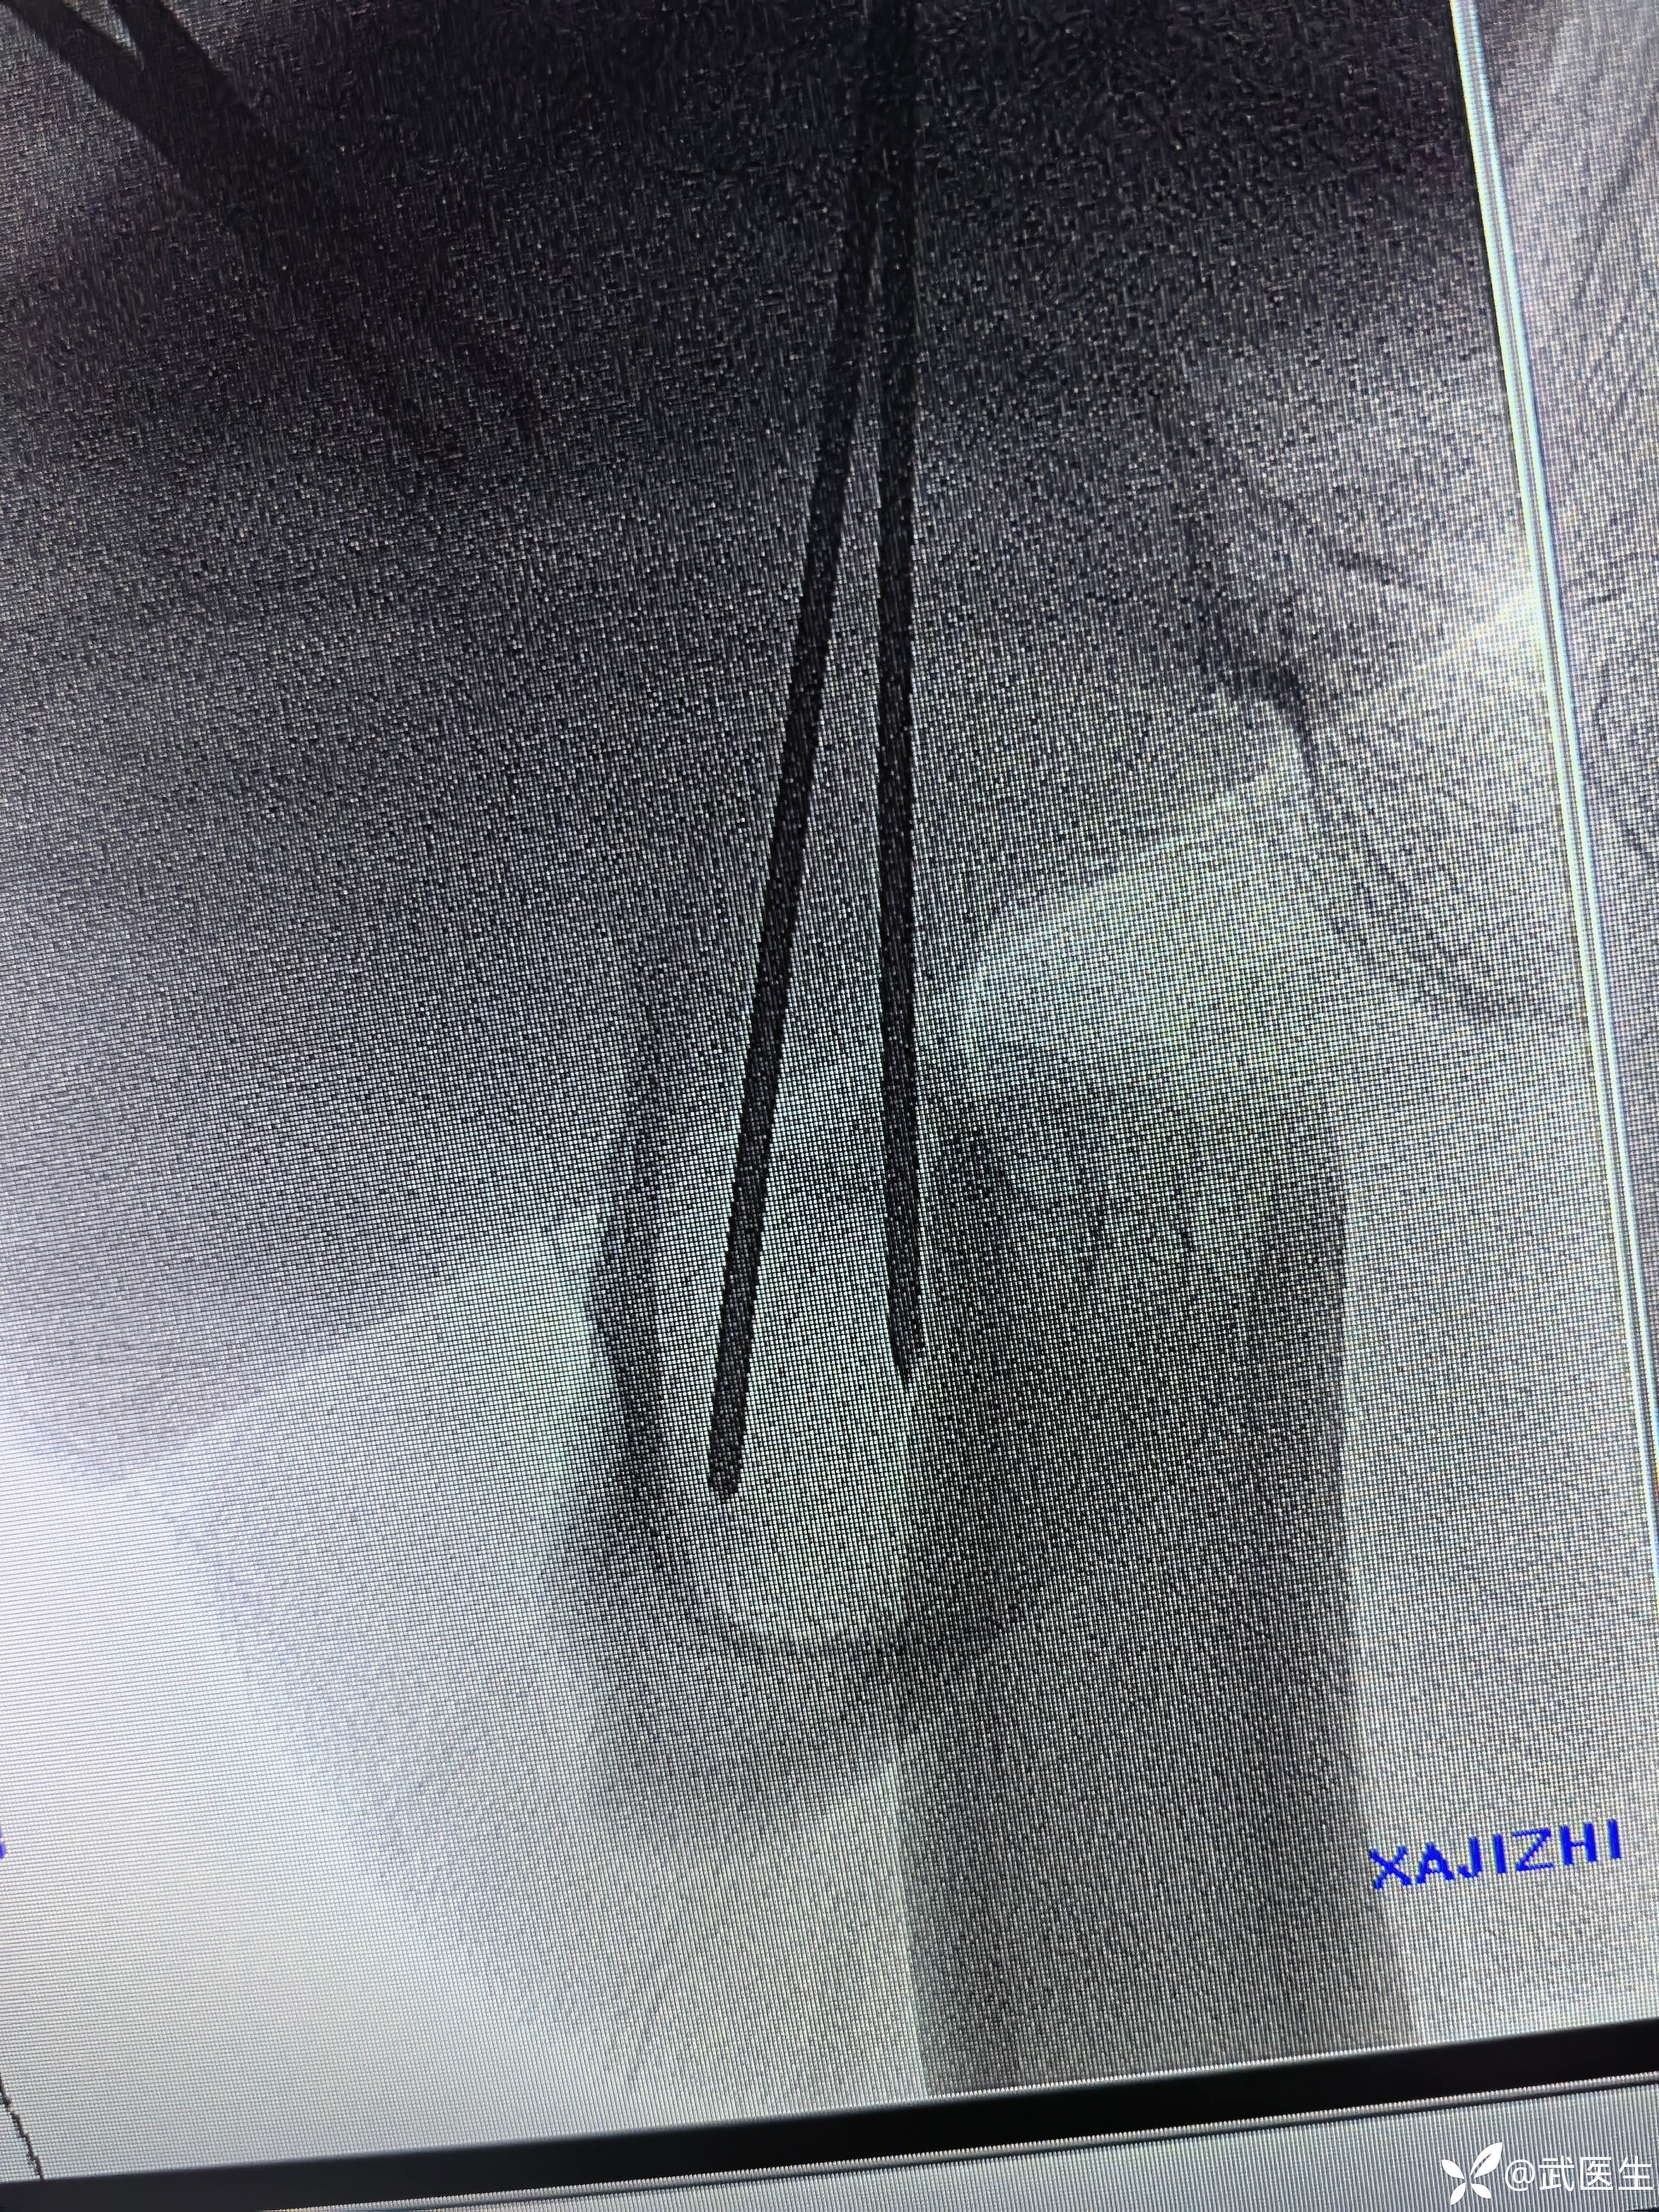

利用金手指置入导针,扩髓,步骤省略

置入合适髓内钉,如下

断端向外成角,对位不好,经常出现的问题,退出髓内钉,打阻挡克氏针,

置入

成角纠正,断端间隙有点大